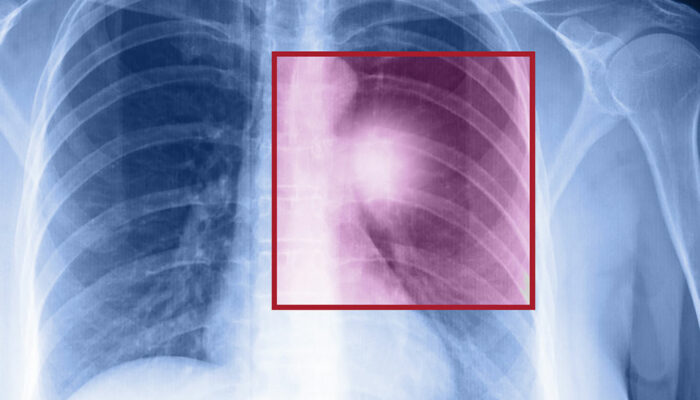

Lung cancer – Types, symptoms, and causes

When the cells in the lungs begin to abnormally multiply and grow, it results in cancer. Lung cancer is one of the leading causes of death in the world. And the risk of suffering from this life-threatening disease is even higher when one is a smoker. Herein, we discuss the various factors that come into play when it comes to lung cancer. Symptoms of lung cancer Usually, lung cancer does not present any symptoms or signs in the early stages. However, as the disease progresses, one may notice Headache Bone pain Loss in weight Hoarse voice Chest pain Shortness of breath Coughing of blood A new cough that persists One should consult a doctor if they notice these signs. If someone is unable to quit smoking, they should visit a medical practitioner for quitting techniques to help avoid this disease. Types of lung cancer There are two kinds of lung cancer: Non-small cell lung cancer This is a catchall term that includes many varieties of this disease, like large cell carcinoma, squamous cell carcinoma, and adenocarcinoma. Small cell lung cancer This happens mainly to people who are heavy smokers, and it’s rarer than non-small cell lung cancer. Risk factors of lung cancer Various factors put you at risk of getting this disease.